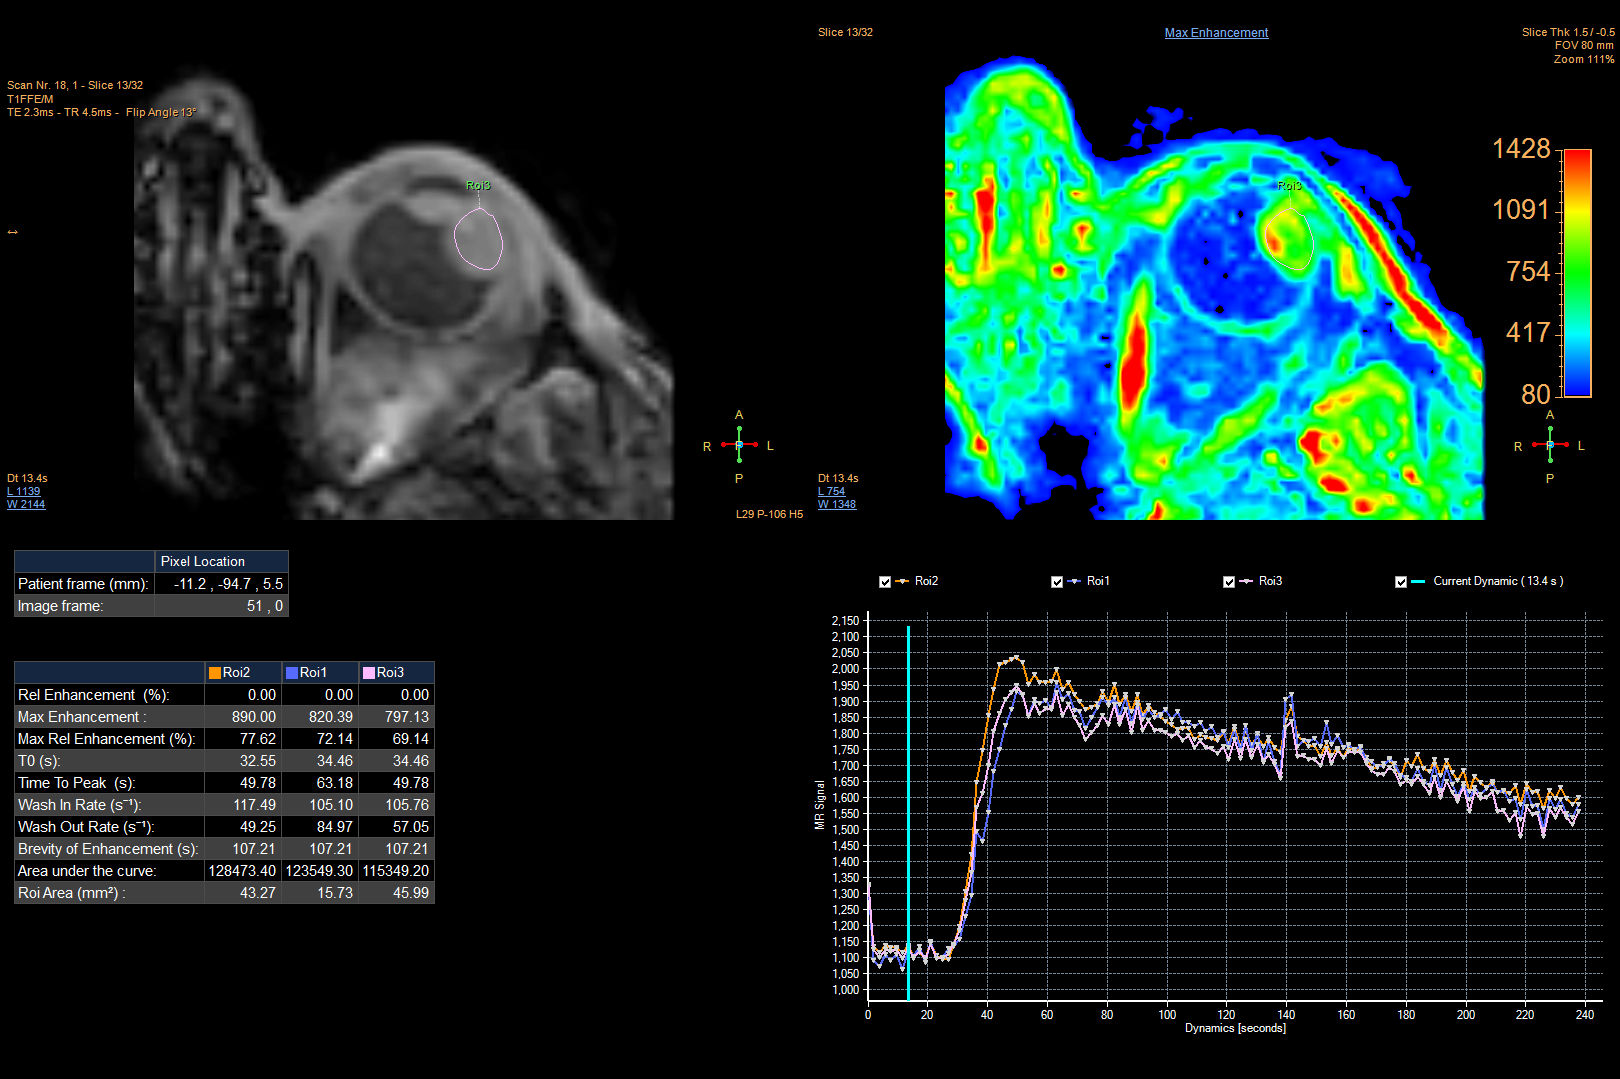

Perfusion and diffusion scans are used for differential diagnosis. The diffusion sequence can help a radiologist confirm whether a tumor is malignant or not and the perfusion results can show the effects of treatment. Using ultrasound to evaluate the effects of treatment takes longer due to post-treatment inflammation.